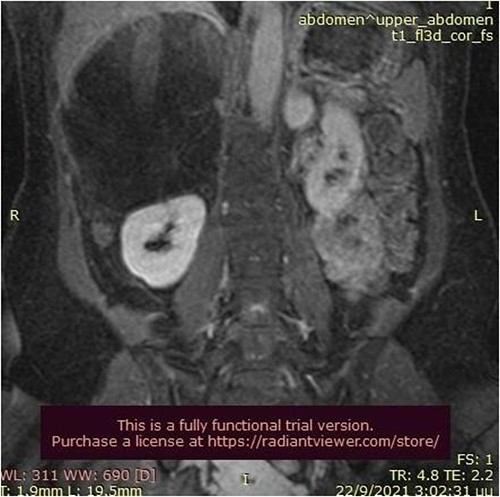

A 50-year-old woman was referred for surgical resection of a large right adrenal mass, which was incidentally found in an ultrasound scan performed for vague abdominal symptoms. Subsequently an abdominal MRI scan depicted a 16 × 15 × 6 cm right adrenal mass with characteristics suggestive of a myelolipoma, without evidence of vascular or periadrenal organ invasion (Figs 1 and 2). The patient underwent a comprehensive hormonal serum testing that confirmed a nonfunctioning adrenal mass. Because of the size of the lesion, an open operative approach was selected. Through a supraumbilical midline incision the mass was carefully dissected from the surrounding structures. It was adherent to the right kidney, the liver and the inferior vena cava without, however, compressing it. The harmonic scalper was used and clipping of the adrenal vasculature as appropriate. Intraoperatively, there was no adverse event. The specimen was removed intact and was sent for histological examination (Fig. 3). A silastic corrugated drain was inserted before closure of the laparotomy. The patient’s postoperative course was unremarkable and she was discharged on the third postoperative day. Histopathology revealed a lesion consisting predominantly of fatty tissue containing all types of hematopoietic stem cells and confirmed the diagnosis of myelolipoma (Figs 4 and 5).

MRI scan depicted a 16 × 15 × 6 cm right adrenal mass with characteristics suggestive of a myelolipoma (transverse plane).